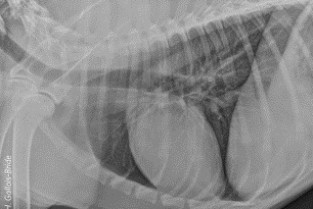

Le GEIM vous propose une séance de travaux pratiques de radiographies sur le thorax. Tous les aspects sont abordés sous la forme de TP de lecture de radiographies numériques sur station de travail Osirix sur Mac (3 vétérinaires maximum/ordinateur).

• décrire les principes à respecter pour obtenir une radiographie thoraciques de bonne qualité ;

• adopter une méthodologie pour interpréter des radiographies thoraciques chez les carnivores domestiques ;

• décrire la radioanatomie du thorax chez les Carnivores domestiques.

Technique et anatomie radiographique du thorax

Sémiologie et interprétation d’une radiographie thoracique

TP de lecture de radiographies numériques sur station de travail